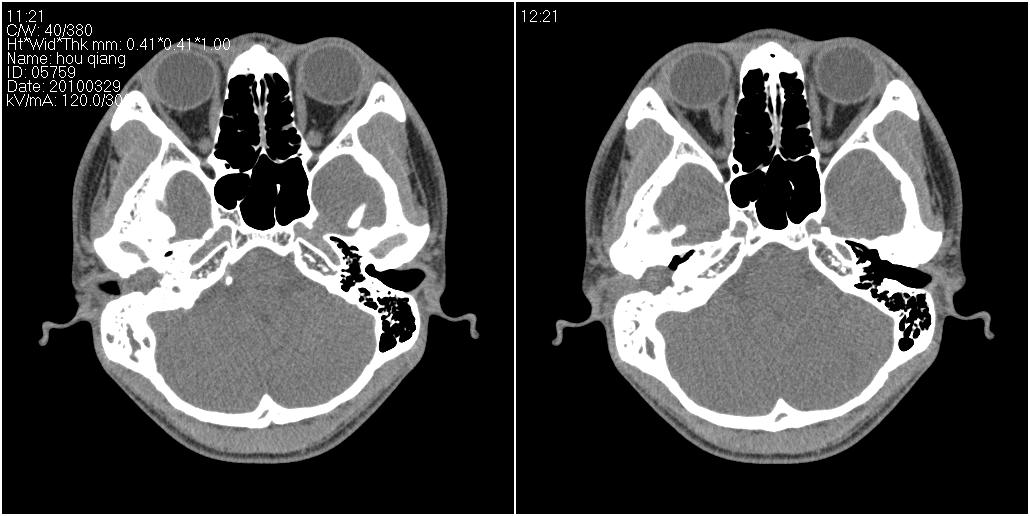

标题: CT25419:男性,18岁。右耳肿、痛5个多月。 [打印本页]

标题: CT25419:男性,18岁。右耳肿、痛5个多月。

右侧中耳乳突炎累及外耳道,鼻咽腺样体肥大。

1)右侧慢性中耳乳突炎并右侧中耳腔及外耳道肉芽肿或胆脂瘤形成。2)鼻咽腺样体肥大。